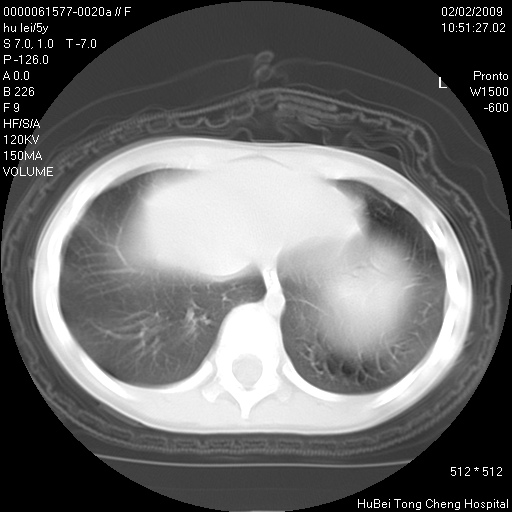

标题: PED1732:M5Y,右肺囊性占位!

患者:男,5。无明显不适,拍胸片考虑右肺囊肿。

行ct扫描,图象如下:

病灶与前胸壁和右上纵隔、叶间裂界限不清,病灶前缘及内侧缘看不到正常的肺组织,不能排除包裹性积液。